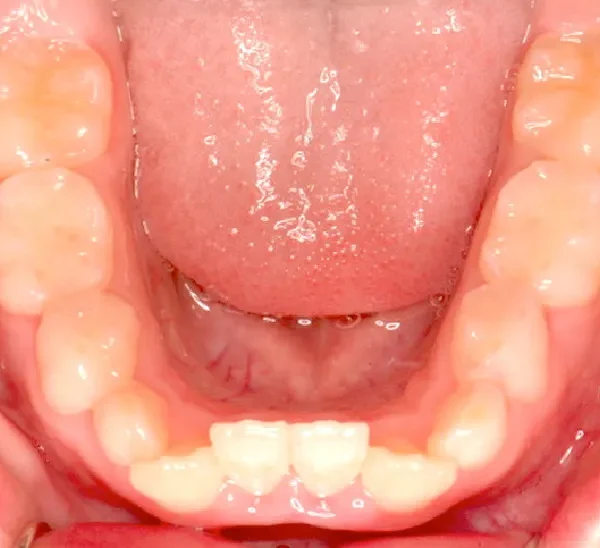

永久歯に生え変わってからはマルチブラケット装置を使用し、噛み合わせ・見た目をしっかり仕上げました。

治療回数42回、4年6ヶ月の治療期間で矯正治療を終了しました。

主訴が改善され、ご満足頂きました。